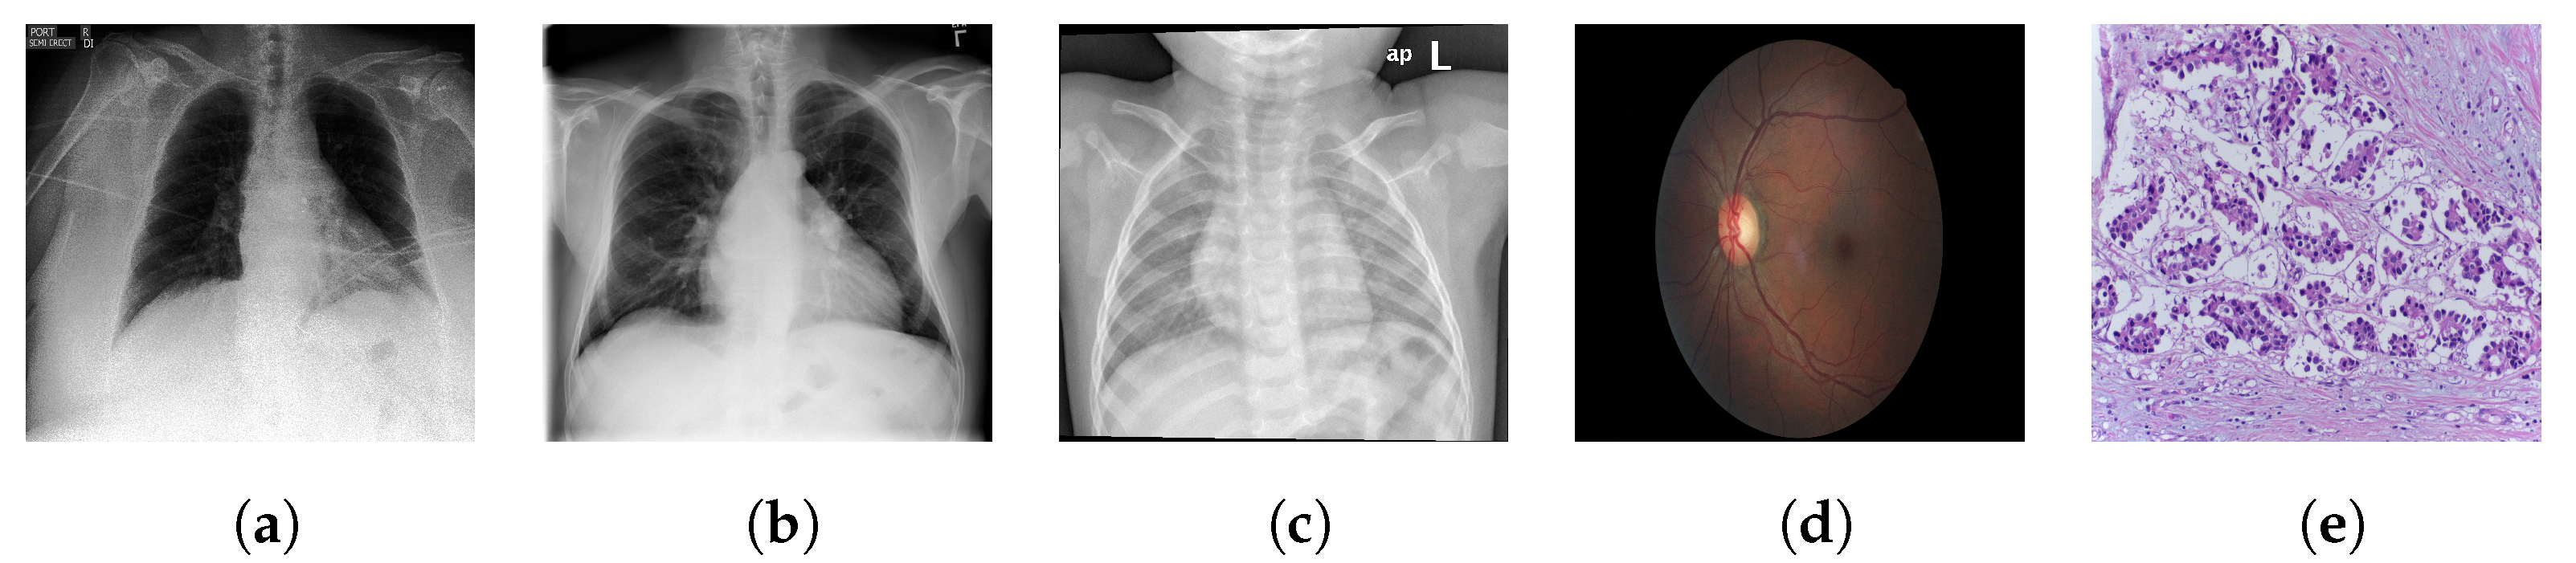

- Medical images differ significantly in their structure to the natural images found in ImageNet, which are non-cluttered and have a clear global object. Many medical images are extremely unstructured, such as skin lesions [21]. Even those with a clearer object-like structure, for example X-rays, have characteristic signatures associated with the different categorical labels (which in a medical context often correspond to different pathologies) that tend to be minute local textural variations [19]. Medical image analysis has therefore proven to be a difficult task for deep learning models. Consequently it provides a strong test of the generalisability and robustness of the features learned by self-supervised pretraining.

| Dataset | Type | # Images | # Classes |

|---|---|---|---|

| CheXpert | CXR | 224,316 | 14 |

| Shenzhen-CXR | CXR | 662 | 2 |

| Montgomery-CXR | CXR | 138 | 2 |

| ChestX-ray14 | CXR | 112,120 | 14 |

| BACH | BHM | 400 | 4 |

| EyePACS | Fundus | 35,126 | 5 |

| iChallenge-AMD | Fundus | 400 | 2 |

| iChallenge-PM | Fundus | 400 | 2 |